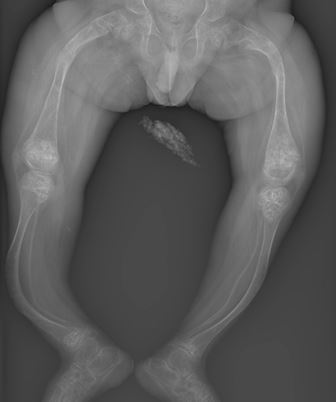

OI otherwise known as ‘brittle bone disease’ is a condition in which bones and other tissues in the body are weak due to defect in the collagen protein. Because of this, bones are unable to withstand mechanical forces and they break easily. This is a genetic disease in which the baby is born with defect in his/her genes and it may be transmitted to the next generation. Risk of such condition is more when marriage occurs between blood relatives (Consanguineous marriage).

There are different types of OI according to severity and genetic defect. In the most severe type of OI babies die within uterus of mother or dies at the time of birth. In the mildest variety there may be a slightly increased risk of sustaining fractures on fall.

- Frequent fractures- in most patients fractures occur even before child starts walking (age of 1 year). Earlier the fracture, more severe the disease. Commonly bones of thigh and leg fracture. Fractures heal at same time as normal children.

- When multiple fractures occur and the healed bone may be short or bent (called ‘bowing’)

- The typical x ray picture helps in diagnosis